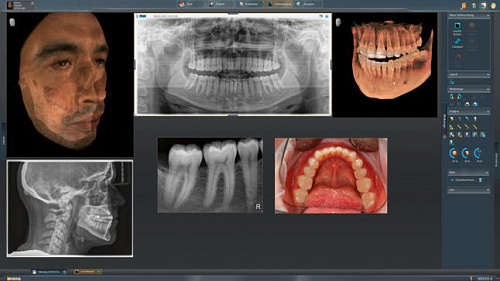

Интегрированная имплантология с GALILEOS Implant

Все манипуляции, связанные с операциями имплантологического плана эффективны и безопасны. Для того чтобы наиболее оптимальным способом спланировать лечение, есть возможность совмещения цифровых слепков и рентгеновских изображений и объединения данных SIDEXIS 4 и CEREC 44.

Анализ дыхательных путей с SICAT Air

Специальная функция привлечёт в вашу клинику людей с проблемами дыхательной системы.

Ортодонтия с CEREC Ortho

Ортодонтические процедуры станут более качественными с установкой установки ORTHOPHOS SL и CEREC.

Благодаря интегрированию в рабочий процесс Sirona специалисты клиники имеют возможность составлять различные схемы лечения, в том числе включая комплексную имплантологию с использованием ПО GALILEOS Implant и хирургических шаблонов (например, шаблонов CEREC 2), а также диагностику и терапию дыхательных путей с помощью SICAT AIR и SICAT OPTISLEEP.